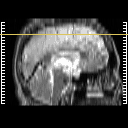

Click on sagittal image to select slice. Click on thin tickmark to change timepoint, or thick tickmark for overlay.